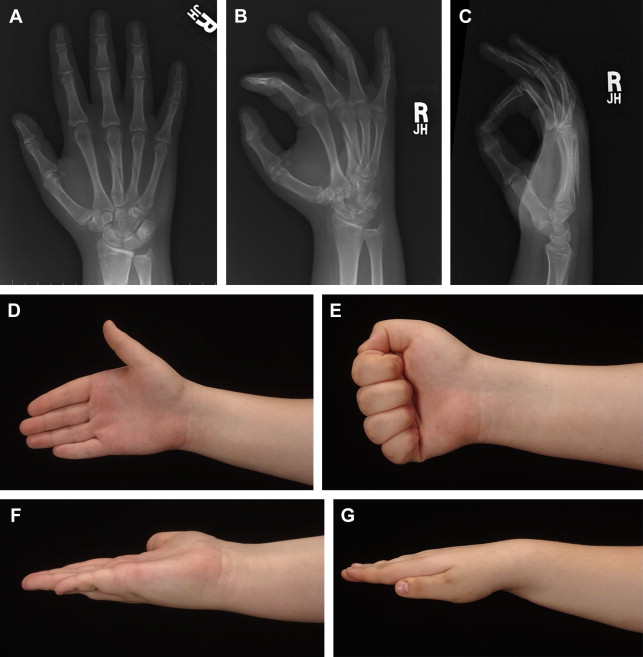

Fig. 1 illustrates a patient that sustained a third metalcarpal spiral fracture that had minimal displacement. The patient wanted surgery, believing it would restore normal function faster. The postreduction with rigid lag screw fixation revealed normal anatomic alignment. The postoperative course, however, was complicated with stiffness that necessitated formal physical therapy. Normal motion was finally obtained but somewhat prolonged (see Fig. 1 ). Similar fractures can be treated conservatively with rapid return to full activities ( Fig. 2 ). Metacarpal neck fractures tolerate conservative management extremely well ( Fig. 3 ). Even metacarpal shaft fractures can be treated in a conservative fashion despite significant dorsal angulation ( Fig. 4 ). These patients must initiate aggressive early motion to maintain normal function. The dorsal hump is usually cosmetic and does not foster physical limitations. Occasionally a palmar prominent metacarpal head can cause tenderness on gripping objects, but this is also uncommon. Multiple metacarpal fractures can also be treated nonoperatively with early active motion ( Fig. 5 ). The key to success is demonstrating normal motion with no scissoring or malalignment and regular follow-up visits. What defines stability of a fracture is an interesting concept. Fractures can be significantly displaced and considered unstable yet still heal with normal function with a conservative approach ( Fig. 6 ). Clinical studies defining the extent of the displacement that will compromise healing or function still need to be done.